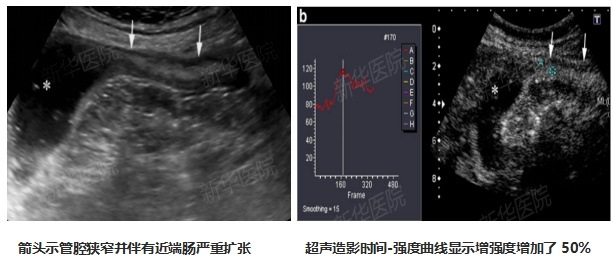

4、超声造影实时成像技术:可动态显示肠壁微循环灌注,具有实时动态、无辐射、无肝肾毒性等独特优势,敏感诊断肠壁炎症活动性、动态监测治疗效果。并且检查前无需特殊肠道准备。

5、超声造影定量分析技术:反映血池超声造影剂的微泡浓度与时间对应的血流灌注信息;客观量化组织或肿瘤的增强方式、避免临床诊断的主观偏倚。超声造影定量分析技术具有灵活、简便、安全性和可重复性。用于IBD诊断、炎症活动性评估及评估治疗反应。

定量分析软件获取病变肠壁微循环灌注的定量参数

6、多模态超声综合评估:可以评估病变肠壁厚度、范围、血流、软硬度,肠腔有无狭窄。若有狭窄,超声造影可清晰地显示狭窄所在的部位,超声剪切波弹性成像可以帮助判断狭窄的类型是炎症性狭窄还是纤维性狭窄,为临床诊疗策略的制定提供影像学依据。